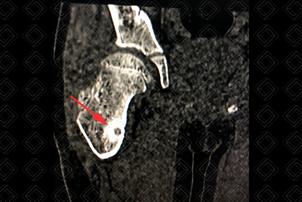

Texto alternativo para a imagem Figuras 1 e 2. Créditos: Dra. Elazir Mota - Rio de Janeiro/RJ

Descrição das figuras 1 e 2: Tomografia computadorizada do quadril direito evidenciando lesão com nidus central (setas vermelhas) na cortical da região metadiafisária do fêmur direito, compatível com osteoma osteoide.

• Tomografia computadorizada: Boa para localizar com precisão o nidus e determinar seu tamanho. Pode ser útil no planejamento de radiologia intervencionista (figuras acima);